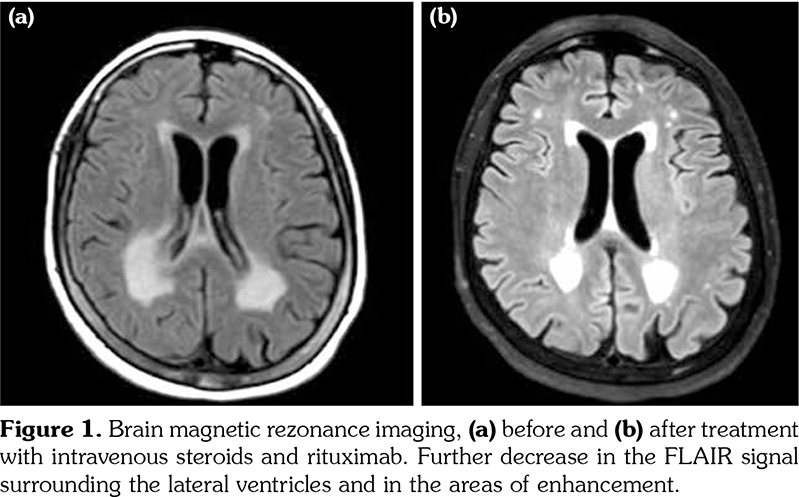

Autoimmunity and the overall state of chronic inflammation are associated with many extra- articular manifestations.(1) Rheumatoid vasculitis is probably the rarest yet the most severe extraarticular manifestation and is usually observed in patients with long-standing, uncontrolled seropositive disease.(2) In this article, we describe the case of a 61-year-old female patient diagnosed with seropositive long-standing rheumatoid arthritis presented to our hospital recently and episodic fluctuations of altered level of consciousness of one week duration, initially diagnosed to have bacterial meningitis based on cerebrospinal fluid analysis with superimposed pneumonia and started on antibiotics with no improvement. Patient is known to have multiple rheumatoid nodules in her chest, followed-up by serial computed tomography scans. Magnetic resonance imaging (MRI) of the brain upon admission showed multiple confluent high fluid- attenuated inversion recovery (FLAIR) signals in the periventricular white matter, hippocampal gyrus and peritrigonal regions of both cerebral hemispheres (Figure 1). In light of the patient’s known diagnosis of rheumatoid arthritis, these findings were compatible with an inflammatory process consistent with rheumatoid vasculitis. Repeated cerebrospinal fluid analysis after antibiotics treatment indicated increased number of inflammatory cells, mainly lymphocytes and monocytes. Open lung biopsy revealed active chronic interstitial pneumonitis (Figure 2). It was then decided to start our patient on steroids: intravenous methylprednisolone 40 mg push twice daily and antibiotics were discontinued with the diagnosis of rheumatoid cerebral vasculitis. She was then discharged on prednisone 40 mg orally once daily.